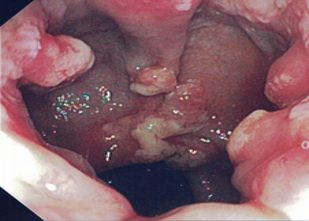

Colonoscopy was done, the results of which showed that changes were limited to the rectum (Figure 1). The rest of the colon and the terminal ileum were normal.

Figure 1. Colonoscopy findings at presentation showing multiple polypoidal lesions with whitish gray exudate covering the apical portions of the polyps, with surrounding erythema and friability.